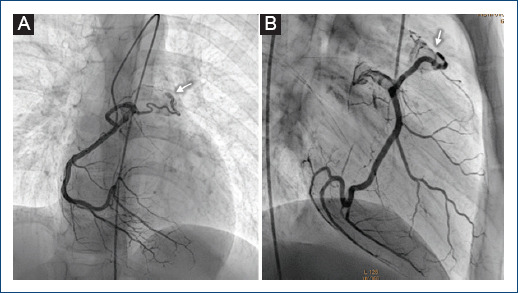

[Double coronary fistula: a rare finding in a pediatric patient].